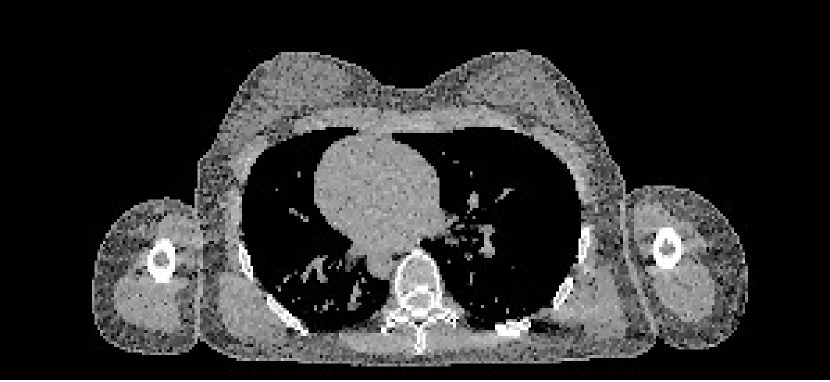

4.3 Cone-Beam CT Validation

To validate our method, we also tested its ability to perform quantitative reconstruction from real X-ray cone-beam CT (CBCT) measurements. For this, we acquired a scan with a Varian® TrueBeam™ On-Board Imager® of a CIRS STEEV head phantom. The phantom consists of synthetic resins to mimic the attenuating properties of human tissues, allowing quantitative assessment of relative electron density accuracy. There was also a metal structure in the centre of the phantom, consisting of the plug section from a PTW PinPoint® ionisation chamber, allowing us to investigate the mitigation of metal induced artefacts.

4.3.1 CBCT Data Processing

4.3.2 CBCT Reconstruction

For reconstruction, we mapped into a resolution of 512×512×144512512144512\times 512\times 144, and used each method as detailed in Section 4.2.1. We ran each iterative method for 500 iterations. For the regularisation parameter, we heuristically used 0.5λpelvis0.5subscript𝜆pelvis0.5\lambda_{\textrm{pelvis}}, where λpelvissubscript𝜆pelvis\lambda_{\textrm{pelvis}} were the same TV regularisation parameters from the digital pelvis experiment, and gave good empirical performance on the CBCT data. Finally, for the bone and metal segmentations required for Poly-SIR, we obtained these through applying thresholds on the FBP and PWLS separately. To illustrate the critical role of this step, we have shown both images in Figures 11(c) and 11(d).

Refer to caption

(a) FBP CBCT

(b) PWLS CBCT

(c) Poly-SIR CBCT 1

(d) Poly-SIR CBCT 2

(e) IMPACT CBCT

(f) Polyquant CBCT

Figure 11: Results from electron density reconstruction from real CBCT data showing slice 83, where each is shown with display window [0.7,1.4]: (c) is Poly-SIR given a bone and metal segmentation derived from the FBP; (d) uses a segmentation derived from the PWLS